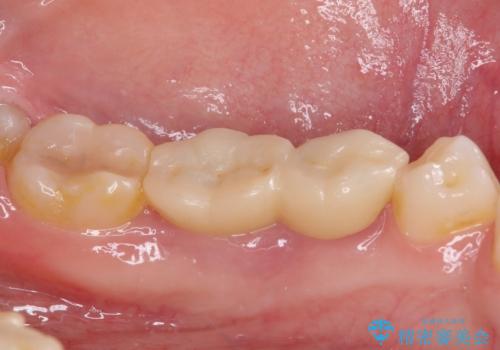

当初は歯肉が腫れ上がり、大変不快な思いをされていましたが、セラミッククラウン装着後は清掃性が著しく改善し、患者様には大変満足していただきました。